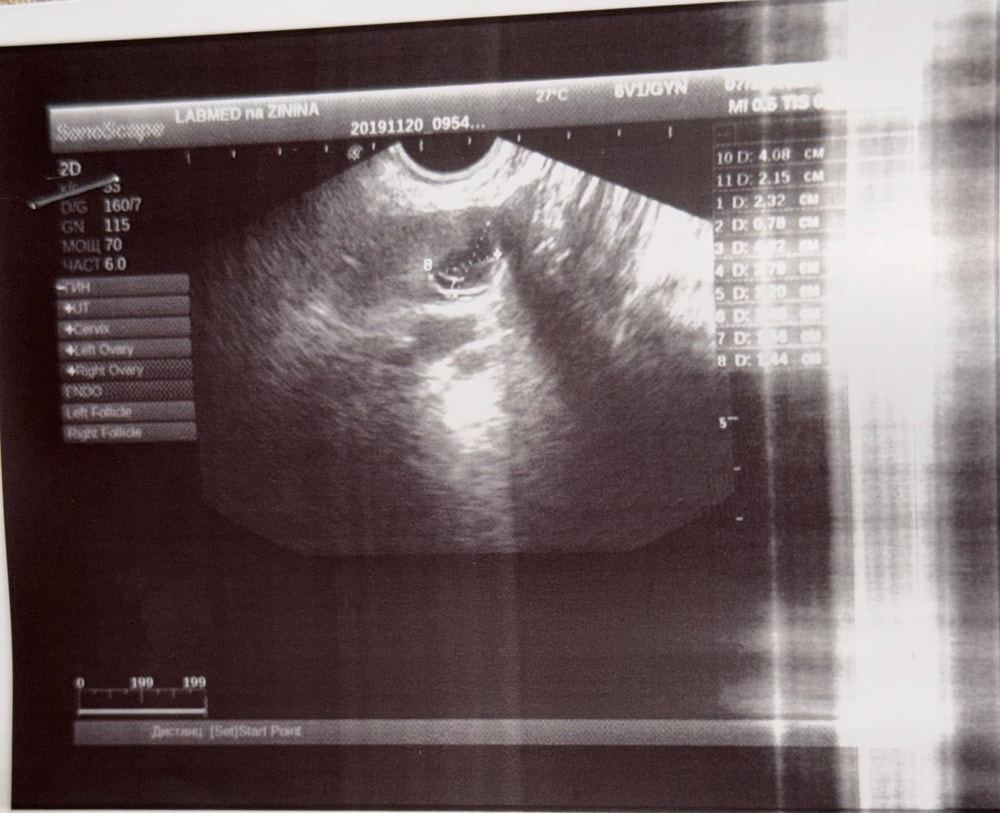

мне дали узи, там какое-то образование ахаха на снимке, но врач ничего не сказала. А на листке просто написано, что цикл овуляторный, обнаружено желтое тело 14 мм в левом яичнике. На снимке оно или плодное яйцо, как думаете?

ДОПОЛНЯЮ СНИМКОМ УЗИ

Ой, могу фото прикрепить в комментарии. Смотрим🤣